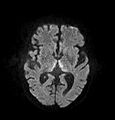

Brain atrophy associated with WKS occurs in the following regions of the brain: the mammillary bodies, the thalamus, the periaqueductal grey, the walls of the 3rd ventricle, the floor of the 4th ventricle, the cerebellum, and the frontal lobe. In addition to the damage seen in these areas there have been reports of damage to cortex, although it was noted that this may be due to the direct toxic effects of alcohol as opposed to thiamine deficiency that has been attributed as the underlying cause of Wernicke-Korsakoff Syndrome.[25]

The amnesia that is associated with this syndrome is a result of the atrophy in the structures of the diencephalon (the thalamus, hypothalamus and mammillary bodies), and is similar to amnesia that is presented as a result of other cases of damage to the medial temporal lobe.[26] It has been argued that the memory impairments can occur as a result of damage along any part of the mammillo-thalamic tract, which explains how WKS can develop in patients with damage exclusively to either the thalamus or the mammillary bodies.[25]

Frequently, secondary to thiamine deficiency and subsequent cytotoxic edema in Wernicke encephalopathy, patients will have marked degeneration of the mammillary bodies. Thiamine (vitamin B1) is an essential coenzyme in carbohydrate metabolism and is also a regulator of osmotic gradient. Its deficiency may cause swelling of the intracellular space and local disruption of the blood-brain barrier. Brain tissue is very sensitive to changes in electrolytes and pressure and edema can be cytotoxic. In Wernicke this occurs specifically in the mammillary bodies, medial thalami, tectal plate, and periaqueductal areas. Sufferers may also exhibit a dislike for sunlight and so may wish to stay indoors with the lights off. The mechanism of this degeneration is unknown, but it supports the current neurological theory that the mammillary bodies play a role in various "memory circuits" within the brain. An example of a memory circuit is the Papez circuit.